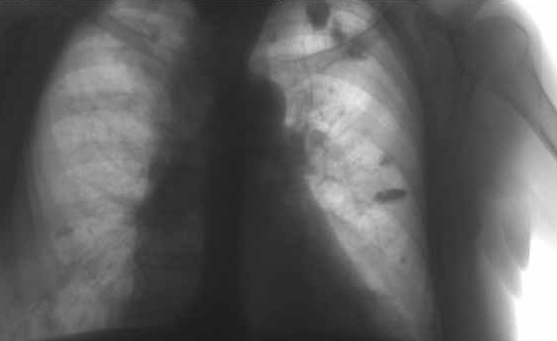

Своєчасне виявлення туберкульозу є вирішальним фактором для ефективного лікування та попередження поширення його серед людей. Рання діагностика виявляє початкові форми туберкульозу (без розпаду легеневої тканини та виділення паличок Коха).

Чим раніше виявлено захворювання, тим більше шансів на повне одужання при умові ефективного лікування. Використовуються загальноприйняті методи виявлення туберкульозу: туберкулінодіагностика (реакція Манту), флюорографічне обстеження та лабораторні методи. Позитивна реакція Манту – наявність папули (інфільтрат) діаметром 5 і більше мм. Негативна реакція проби Манту спостерігається у здорових, неінфікованих мікобактеріями туберкульозу людей. Чим старші за віком особи, тим менше серед них неінфікованих. Так, у 40-річних тільки 5-10% людей негативно реагують на туберкульозний антиген.

З метою своєчасного і раннього виявлення захворювання встановлено періодичне (1 раз на 1-2 роки) флюорографічне обстеження дорослого населення та щорічне проведення туберкулінових проб у дітей. Щорічним флюорообстеженням підлягає населення, яке має підвищений ризик захворіти на туберкульоз.